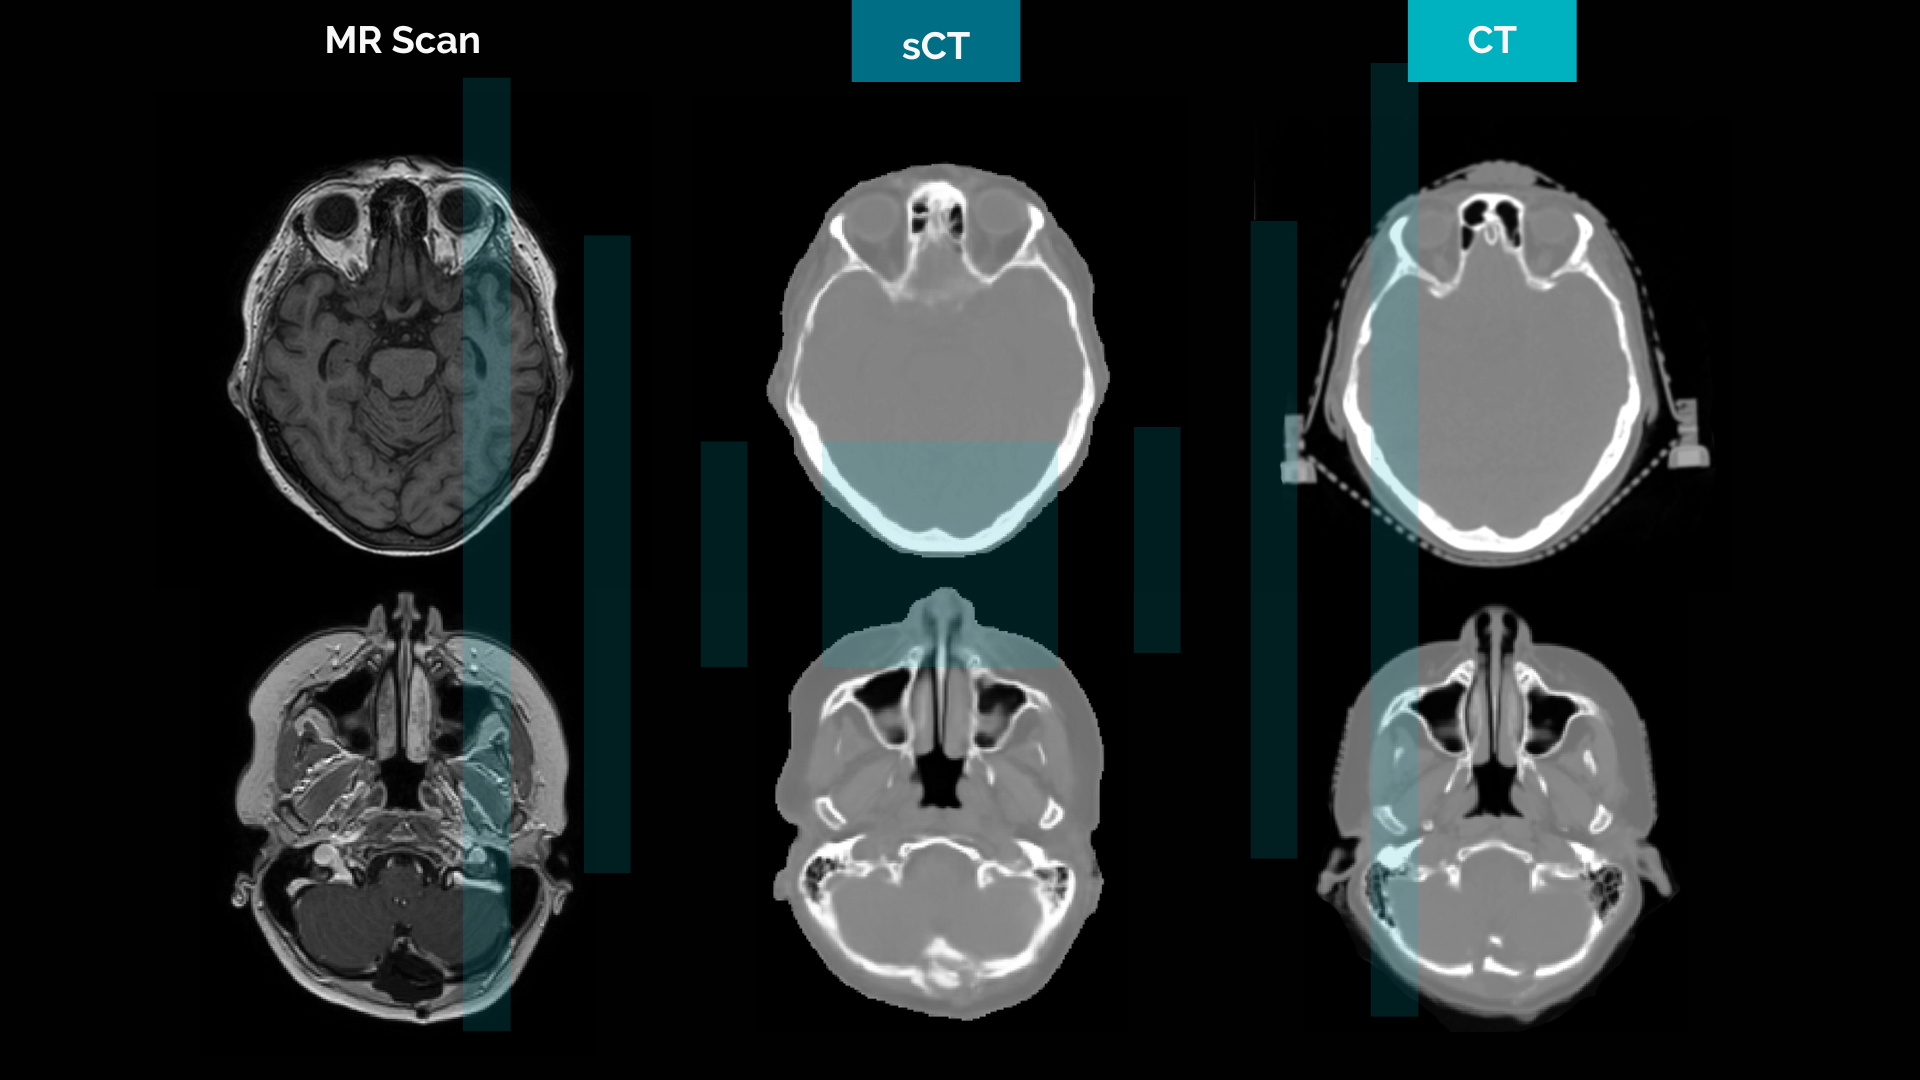

Generative adversarial networks (GANs) are a class of generative models that can be used for various synthetic data generation tasks. GANs have gained a lot of interest in recent years due to their impressive results in image generation², including image-to-image translation³′⁴. A GAN model consists of at least one generator network and a discriminator network. Figure 2 illustrates the training of a GAN model for MR-to-CT translation with training data consisting of pairs of real MR and CT images. The generator takes real MR images as input and generates synthetic CT images. The discriminator learns to classify real and synthetic CT images as real or fake. This drives the generator to learn to generate more realistic synthetic images that are indistinguishable from real images. The training of a GAN can be seen as a competition between the two networks, the generator and the discriminator, where the generator attempts to fool the discriminator.

Due to its inherent superior soft tissue contrast over CT and the development of high-fidelity machines, MR has become a popular imaging modality in radiotherapy. However, because dose calculation algorithms require a correlation between image intensities and high-energy photon beam attenuation, CT images are still used as the main modality for radiation therapy planning. The capability to generate synthetic CT from specific MR sequences makes MR-only workflows possible in external beam radiotherapy, eliminating the need for dedicated CT imaging. Many developments have been published in the literature and some AI and non-AI commercial products are now used in clinics. With an exhaustive high-quality training dataset, deep learning (DL) -based models tend to produce more realistic-looking synthetic CT images in comparison to standard classification methods. However, since GANs and other DL-based methods may sometimes fail (producing errors or artifacts), the need for automatic methods to validate and verify the fidelity of the generated synthetic images becomes important.